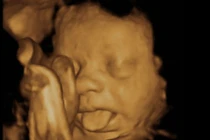

| Thai nhi giống ông vua nhạc Pop Michael Jackson. Năm 2009, đôi vợ chồng Dawn Kelley và William Hickman đã vô cùng ngỡ ngàng khi bức hình siêu âm đứa con gái 24 tuần tuổi của họ trông khá giống ông hoàng nhạc Pop Michael Jackson. Tuy nhiên, em bé sinh ra không giống như hình siêu âm. |